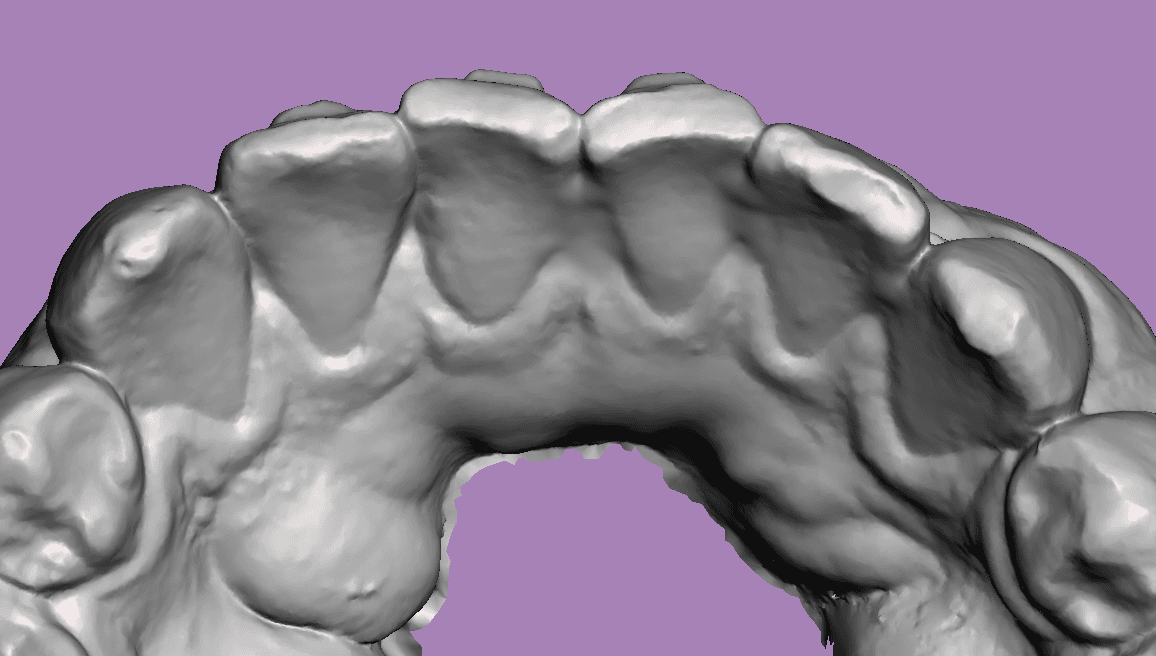

Escaneamento sem contenção

Escaneamento com contenção removida virtualmente

Quanto maior a precisão da cópia do nosso escaner maior será a acurácia da movimentação planejada.